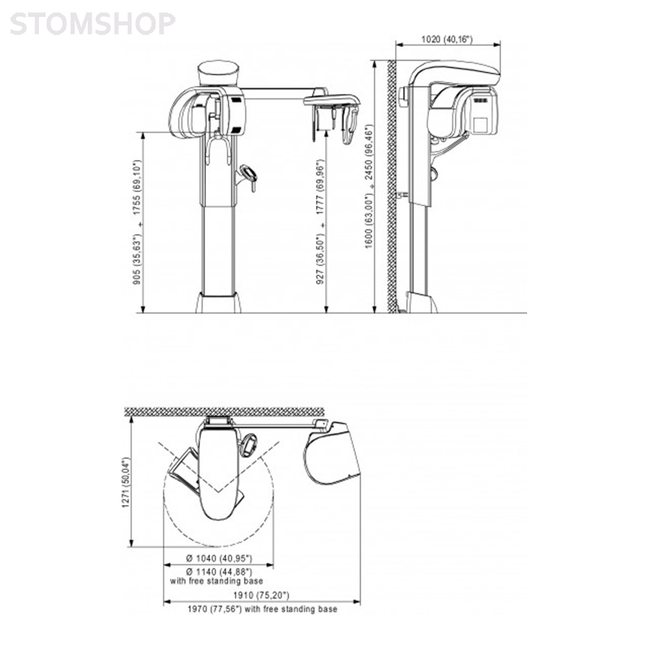

| Вес упаковки | 161.00 кг |

| Габариты упаковки (Д x Ш x В) | x 1,020.00 мм x 4,050.00 мм |